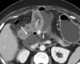

Mesenteric neoplasm